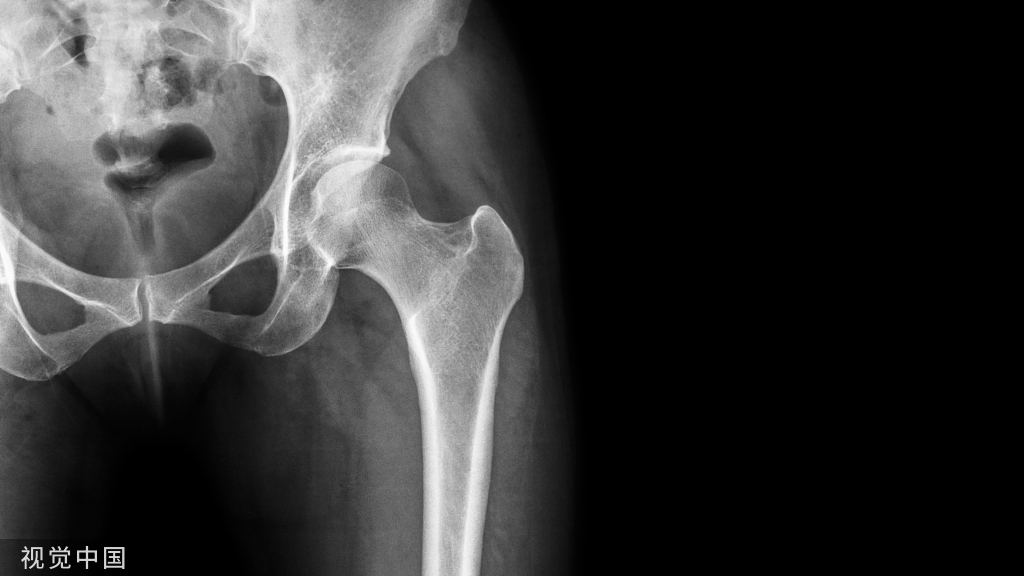

3. 脆性骨折:多数患者早期无明显症状,骨折后经 X线或骨密度检查才发现已有骨质疏松。患者在轻创伤或非暴力情况下(如轻微跌倒或因其他日常活动)发生骨折即为脆性骨折。骨折常见部位为胸椎、腰椎、髋部、桡尺骨远端和肱骨近端。发生一次脆性骨折后,再次骨折的风险即明显增加。

椎体更易发生骨折,这是因为脊椎椎体的松质骨和皮质骨对糖皮质激素较为敏感,激素对松质骨的影响大于皮质骨。

口服激素患者的椎体、髋关节及非椎体骨折的风险分别是非全身性激素治疗对照组的2.60倍、1.61倍和1.33倍。3. 骨折风险与骨密度无线性关系